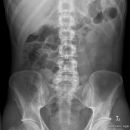

Abdomen

Abdomen im Liegen / a.p. oder p.a. in Seitenlage

Abdomen im Stehen

Indikation

Akutes Abdomen, Ileus, Fremdkörper, Konkremente (Gallen-, Nierensteine), Kontrolle von Fremdmaterialen (Magen-, Duodenal-, Dünndarmsonden, ventrikuloperitonealer Shunt...)

Beurteilungskriterien

• Freie Luftsicheln unter den Zwerchfellschenkel? → perforiertes Magenulcus, Dickdarmperforation (ischämisch, tumorbedingt, entzündlich, Divertikulitis), perforierte Appendicitis, postoperativ? DD Chilaiditi-Syndrom: Coloninterposition zwischen Leber und Zwerchfell – Haustrierung?

• Luft-Flüssigkeitsspiegel? Zentral gelegene Dünndarmspiegel, Arkardenbildung, Distension der Dünndarmschlingen > 3 cm → V.a. Dünndarmileus (zusätzlich) Spiegel entlang des Colonrahmens → V.a. Dickdarmileus Spiegel in Dünn- und Dickdarm, keine ausgeprägte Distension → V.a. Paralyse

• Darmgasverteilung?

Cave: Beim Erwachsenen finden sich normalerweise keine größeren Luftmengen im Dünndarm, wohingegen dies bei Säuglingen/Kleinkindern physiologisch ist. Luft im Dünndarm → Gastroenteritis, Ileus, Peritonitis?

• Psoasschatten? Fehlende Abgrenzbarkeit des Psoasschattens → V.a. retroperitoneale Tumorausbreitung, Abszess, Einblutung auffällig scharfe Abgrenzbarkeit bei Pneumoretroperitoneum → perforiertes Duodenalulcus, Duodenalruptur, Infektion mit Gasbildnern

• Luft in Gallenwegen oder Pfortadersystem? Aerobilie: z.B. bei Gallensteinperforation in den Darm, Z.n. Papillotomie, bei biliodigestiver Anastomose, emphysematöse Cholezystitis Portalvenöses Gas bei Darmgangrän.

• Koprostase? Umschriebene Raumforderungen? Diffuse Verdichtungen, wie z.B. bei Aszites?

• Pneumatosis intestinalis? Infektion mit gasbildenden Bakterien, Darmwandgangrän, pseudomembramöse Enterocolitis

• Verkalkungen? Gefäßverkalkungen, Phlebolithen, verkalkte Lymphknoten

• Cholelithiasis, Porzellangallenblase, Echinococcus-Zysten, Leberhämangiom

• abszess, -metastasen (colorectale Karzinome), organisierte Pfortaderthromben

• Milzinfarkt, älteres Milzhämatom, TBC, Milzzysten, Brucellose,

• chronische Pancreatitis, Phäochromozytome,

• Nephrolithiasis, Nierenzellkarzinome, Blasensteine, Bilharziose, Uterusmyome, Appendikolithen

• Kontrastmittelreste?

• Knochen? Cave: bei Traumapatienten sind Querfortsatzfrakturen häufig mit abdominellen Organverletzungen kombiniert!